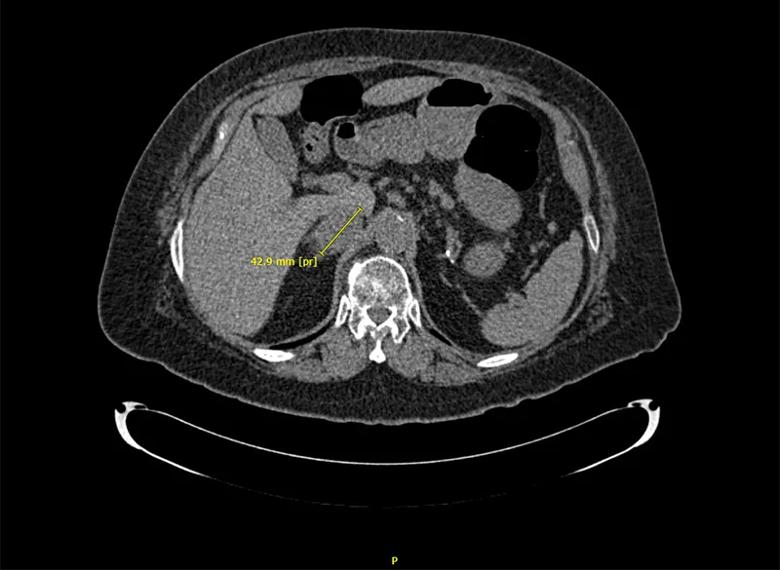

Scan image of patient's tumor

While the patient’s hormone levels were not alarming, the size and indeterminate nature of a large nodule on the right-side adrenal gland raised concerns about malignancy. Dr. Bendaram referred the patient to endocrine surgeon Gustavo Romero Velez, MD, for right-side adrenalectomy.

Laparoscopic en-bloc resection of the gland (10.5 cm x 6.5 cm x 3.4 cm) was done to assure negative margins. The pheochromocytoma measured 5.2 cm x 4.2 cm x 3.5 cm.